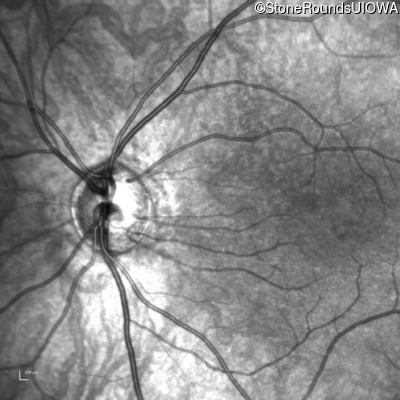

Infrared Fundus Photograph - Right - 10/160 +1 sc

Exemplar